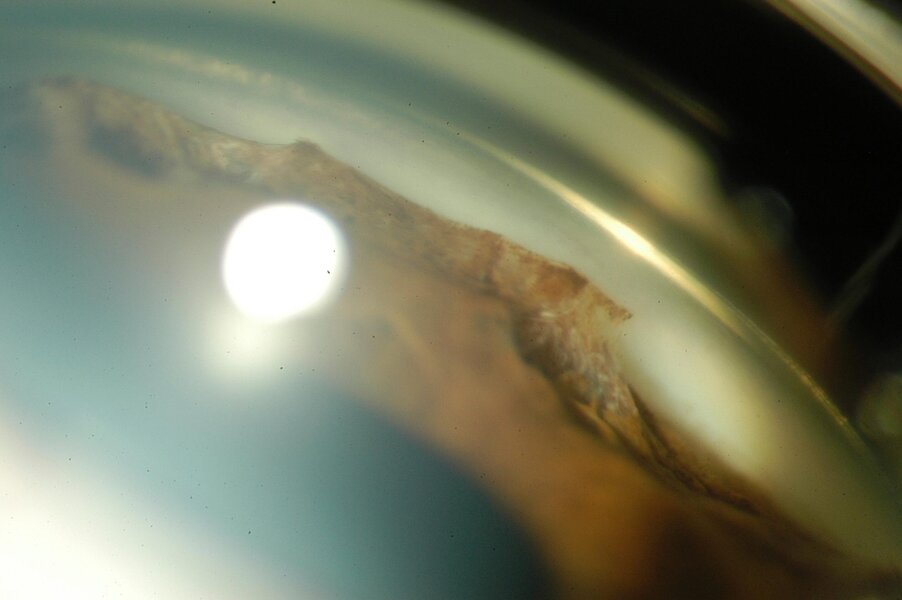

Synéchie dans un ICE syndrome

Le syndrome irido-cornéo-endothélial (ICE), qui englobe l’atrophie essentielle de l’iris, le syndrome de Chandler et le syndrome de Cogan-Reese (ou “iris nævus syndrome”), est le plus souvent unilatéral, non familial et survient typiquement chez la femme jeune. Le syndrome ICE est généralement progressif et se complique fréquemment de glaucome secondaire et de décompensation cornéenne. Dans le syndrome de Chandler, les anomalies iriennes sont moins marquées, et l’œdème de la cornée est plus important que dans l’atrophie essentielle de l’iris ou le syndrome de Cogan-Reese.

(Cliché dû à l’amabilité de Rouland JF, Lille)